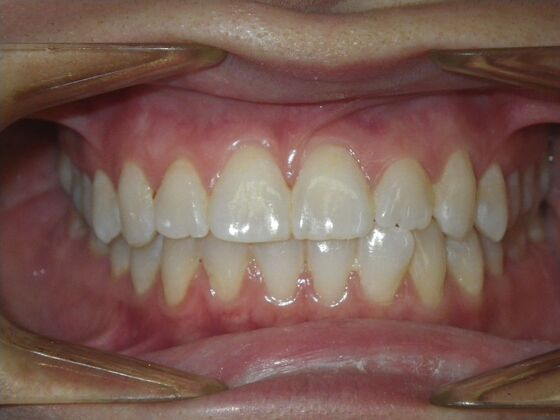

Invisalign: Case 18

This patient had concerns with the lower anterior teeth. There were some slight rotations and the midline of the lower incisors wasn't lined up with the upper midline. To correct this we used slenderizing of teeth in strategic areas of the lower arch to correct the rotations and line up the midlines. Patient very pleased with the results.